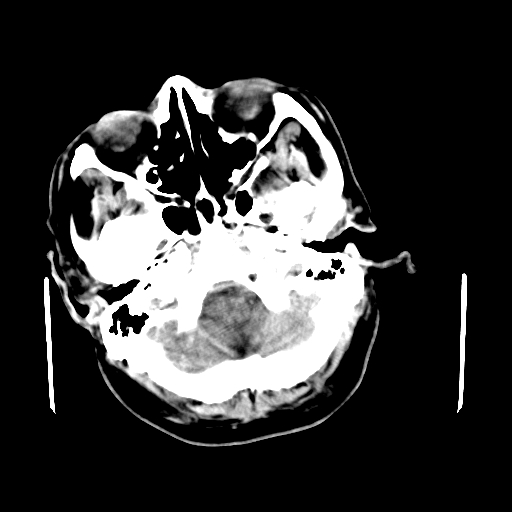

男,62岁,右侧肢体活动障碍不灵活三天,左侧头皮肿物十余年(ct值8hu)。

1)多发性腔隙性脑梗塞。2)脑白质病。3)脑萎缩。4)左侧枕顶部头皮下皮样囊肿,不排除脂肪瘤。